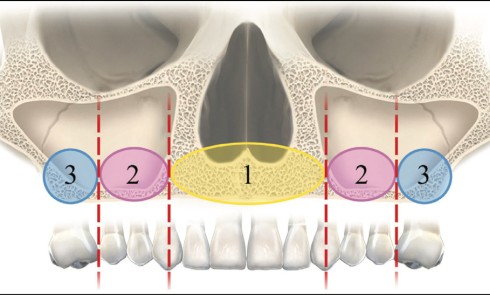

Article réservé à nos abonnés Réhabilitation d’un maxillaire résorbé par quatre implants zygomatiques

Longtemps considérée comme une chirurgie extrême, répondant aux cas de maxillectomie suite à des cancers ou à des personnes accidentées,...